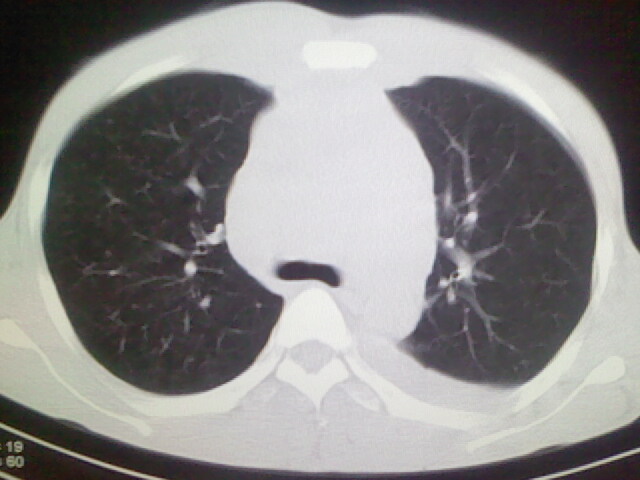

以下是引用杀毒软件在2008-9-3 6:11:00的发言:[br]侵袭性胸腺瘤------一般不侵到气管旁[br][br]考虑----纵隔淋巴瘤,心包及胸膜受累

以下是引用wzr在2008-9-3 5:30:00的发言:[br]侵袭性胸腺瘤

以下是引用随光逐影在2008-9-3 7:07:00的发言:[br]1)考虑淋巴瘤可能。2)双侧胸腔积液(以左侧为甚)。3)心包积液。